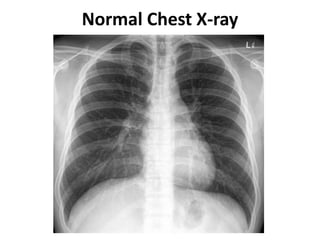

Normal Chest X-ray

Interpreting Chest X-rays

ABCDEFGH approach

• Airway

• Bones & soft tissue

• Cardiac shadow

• Diaphragm

• Effusion (pleura)

• Fields (lungs)

• Gastric bubble

• Hila & mediastinum